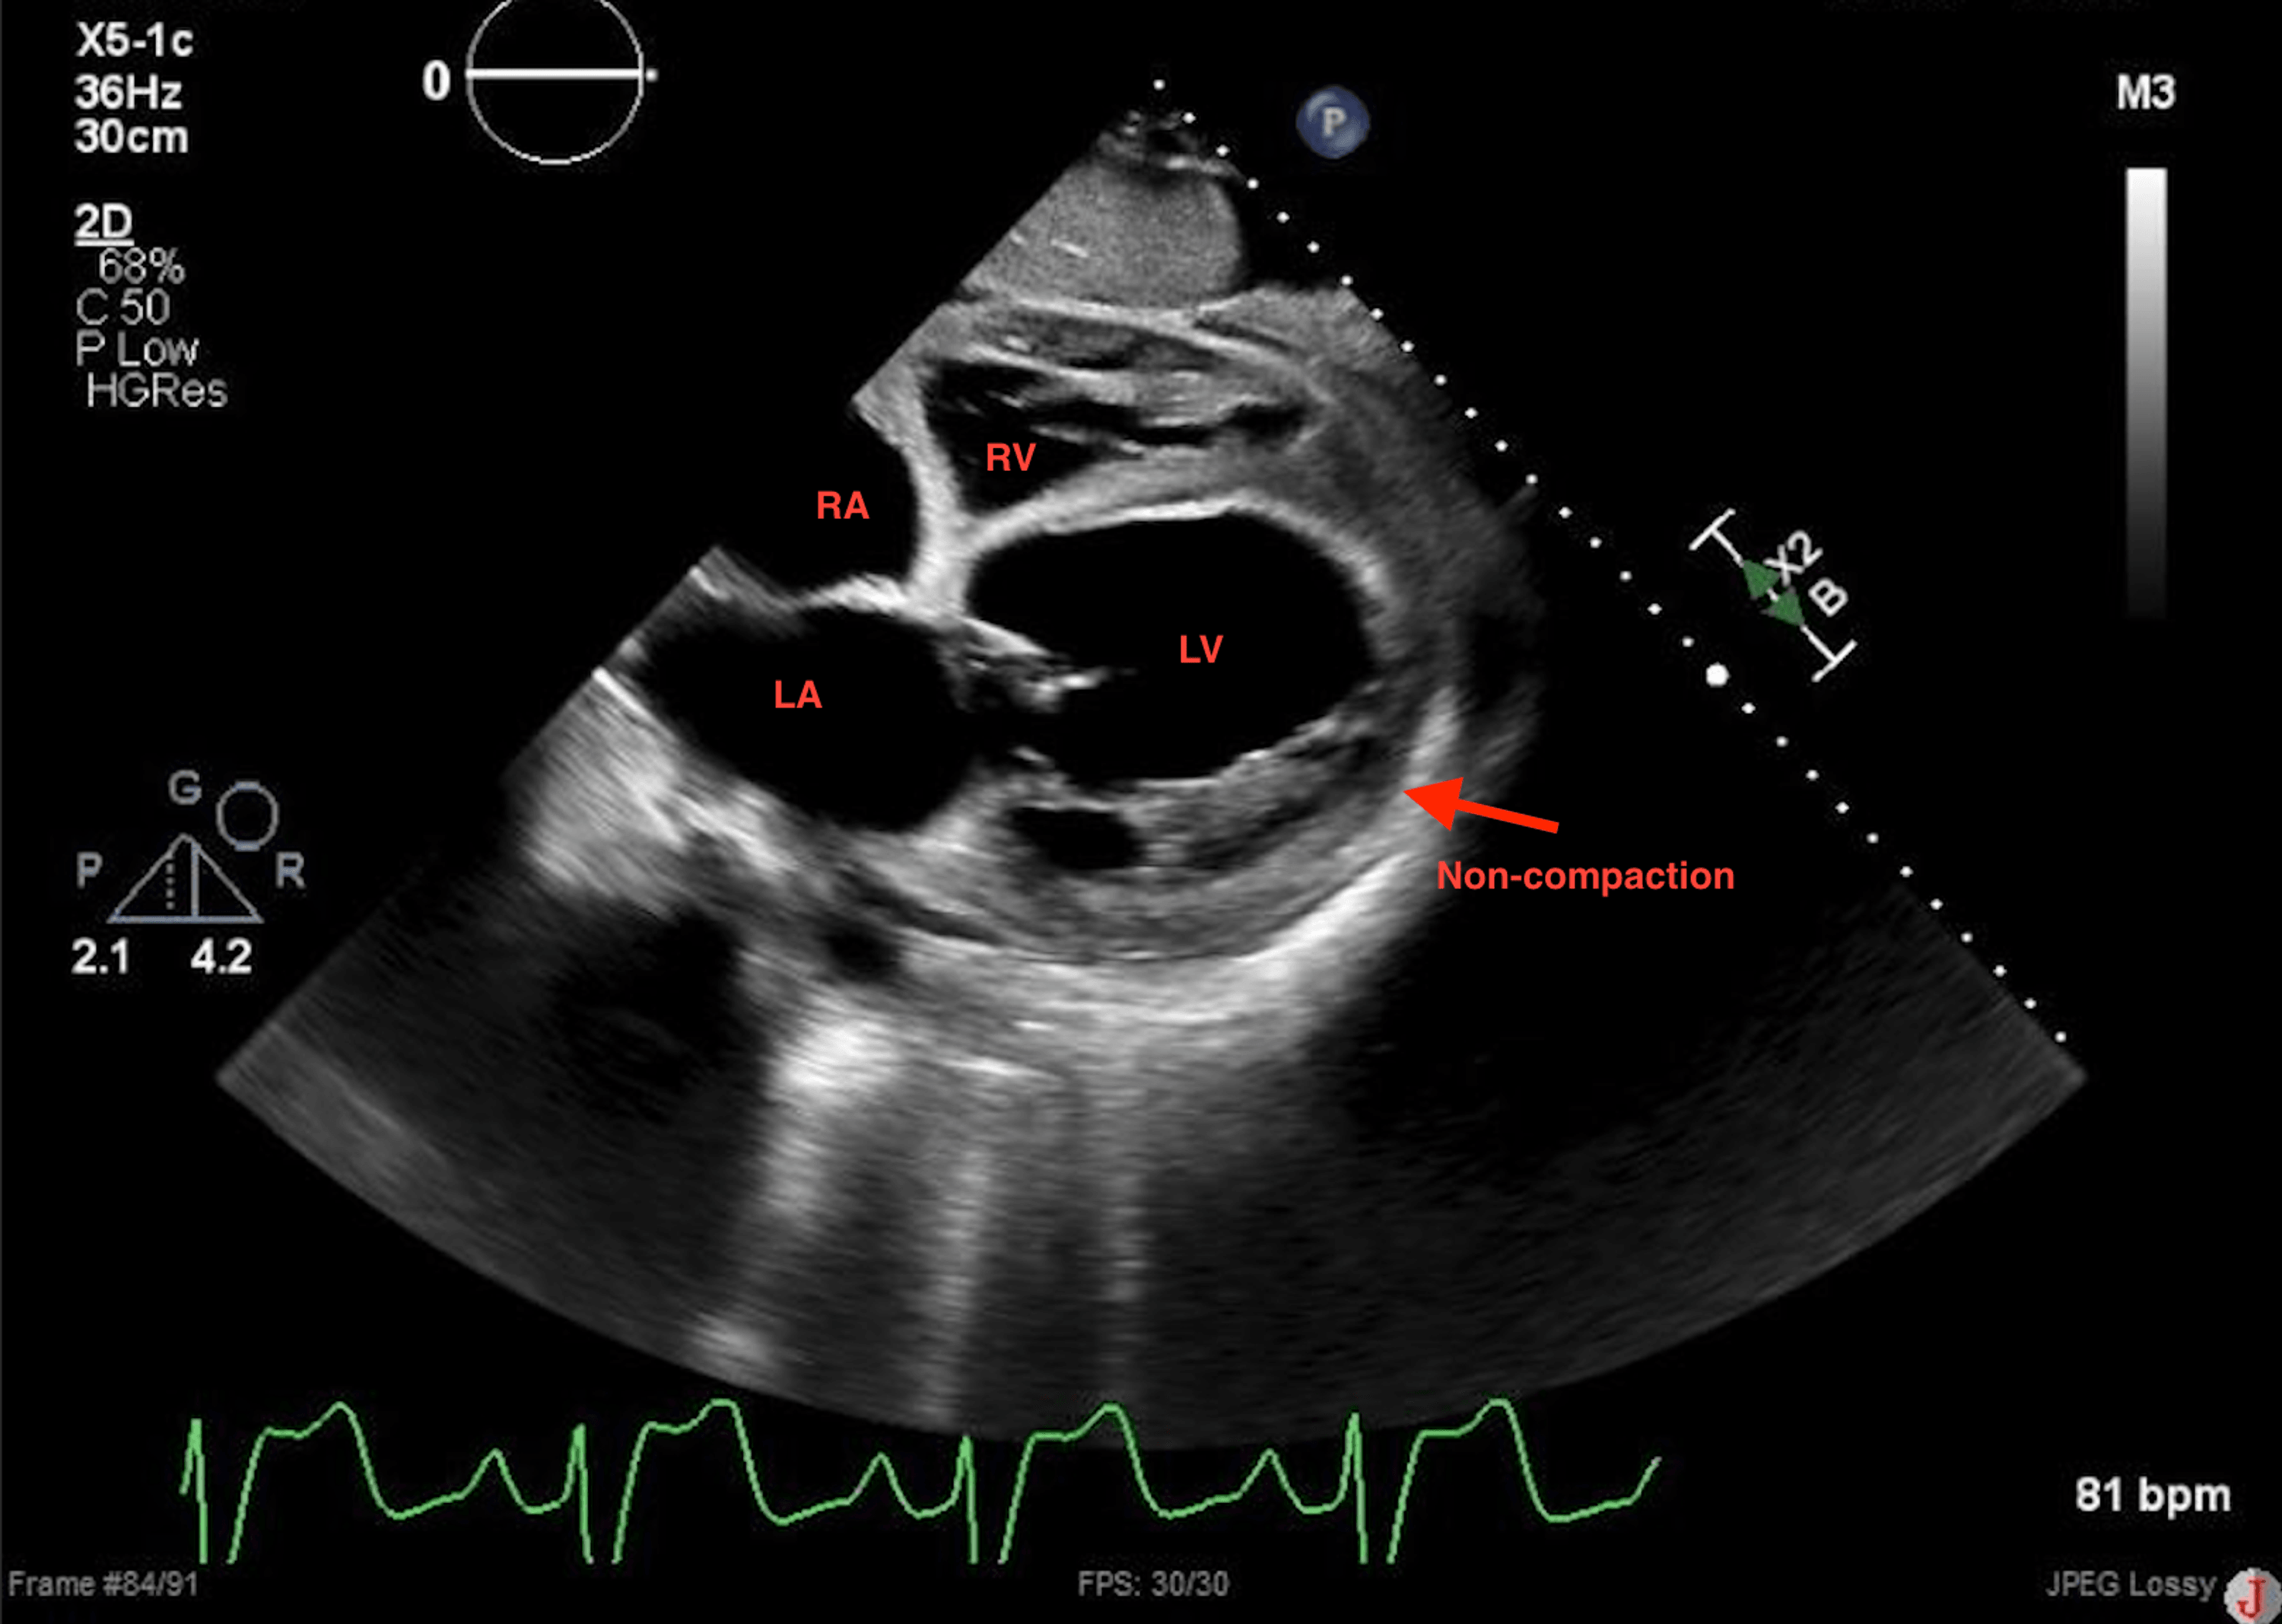

cardiomyopathy. Dilated LV with prominent trabeculation What Is Non Compaction Cardiomyopathy Join our support group for guidance and information. Left ventricular noncompaction (lvnc, also known as noncompaction cardiomyopathy [1]) is a complex myocardial. Symptoms, diagnosis, and management options. Lvnc is a structural heart problem that develops before birth. Later in life, it can cause symptoms like shortness of breath,. What Is Non Compaction Cardiomyopathy.